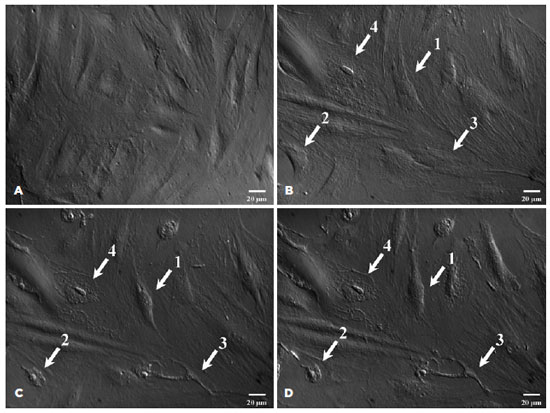

Cells undergo apoptotic morphological changes after UVB irradiation

After UVB irradiation, the cells appeared to exhibit obvious apoptotic morphologies, including (1) cell shrinkage, (2) a decline in cell adherence ability, (3) cell membrane rupture, and (4) nuclear condensation. The 4 cells marked 1, 2, 3, and 4 in figure 1 represent the 4 aforementioned morphological changes. At each time point, 100 cells were chosen randomly, and the 4 types of morphological changes were recorded (Table 2). The apoptotic morphology in the “I (2h) + C (6 h)” and “I (2h) + C (12 h)” groups was more obvious than that in the “I (2h) + C (0 h)” group, and the cell membrane rupture was not recoverable.